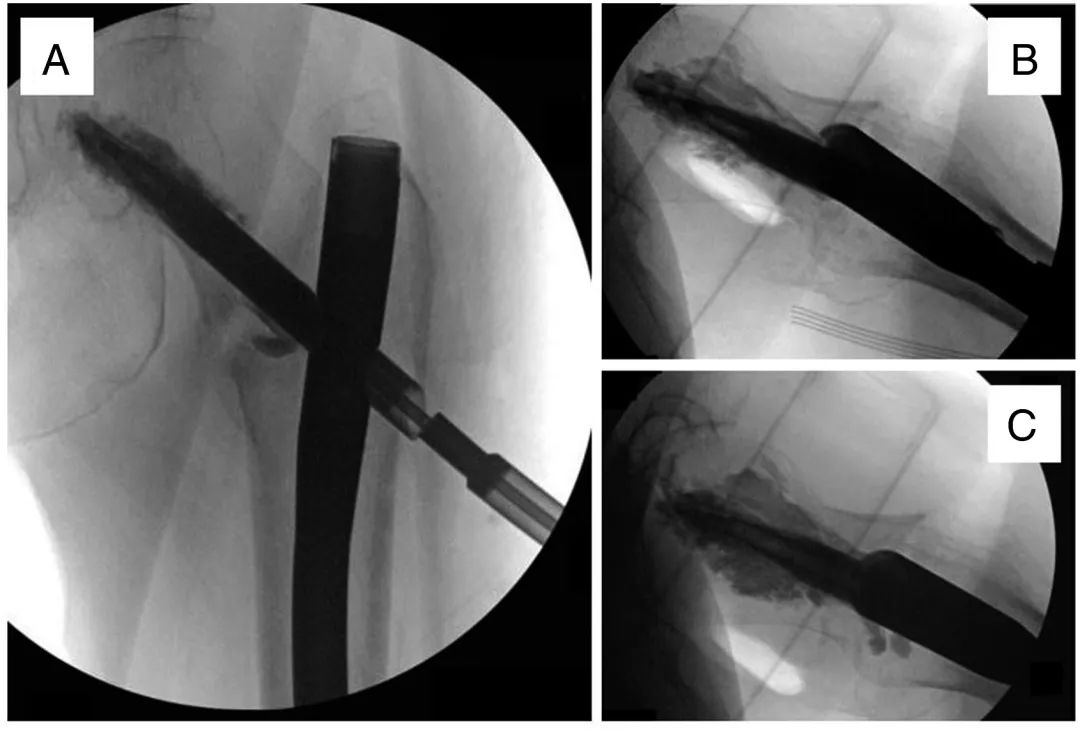

Enfin, la tête fémorale est remplie de ciment osseux à l'aide d'un système de ciment osseux injectable (Figure 6).Des précautions sont prises pour éviter l'extrusion dans l'articulation en utilisant des radiographies en temps réel et en ajustant la profondeur et l'orientation de la canule de ciment.

Figure 6, Imagerie montrant l'augmentation initiale du ciment (A), le remplissage progressif (B) jusqu'à ce que le défaut de la tête fémorale soit comblé (C).